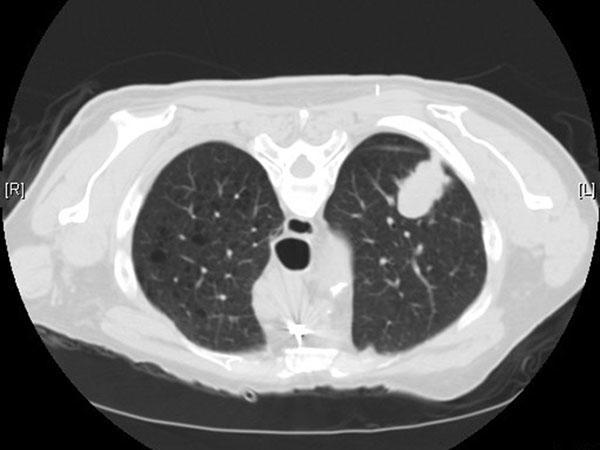

Giải thích nốt phổi dễ hiểu cho cộng đồng: phân loại đặc, kính mờ, bán đặc; nguy cơ ác tính theo kích thước và bờ; khi nào cần chụp PET CT, sinh...